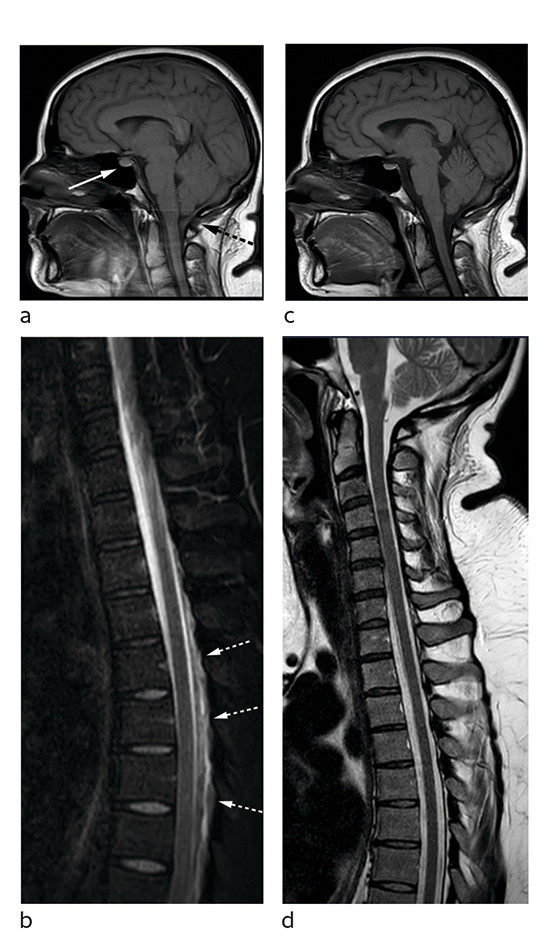

Bildene viser nevroaksen hos en tidligere frisk kvinne i 30-årene. Sagittalt T1-vektet bilde av caput (bilde A) viser forstørret hypofyse (hvit pil) samt at hjernestammen og lillehjernetonsillene har sunket ned mot foramen magnum (stiplet svart pil). Sagittalt T2-vektet, fettsupprimert bilde av cervikotorakalcolumna (bilde B) viser en epidural væskebrem i nivå Th4–Th9 (hvit pil). Det ble også påvist (ikke vist her) fortykkede meninger (FLAIR-serie) og en subdural væskebrem med blodprodukter langs tentoriet (susceptibilitetsvektet serie).

MR-funnene og sykehistorien vekket sterk mistanke om spontan intrakranial hypotensjon (SIH). Pasienten ble i forkant av torakal epidural blodlapp, hvor 20 mL autologt venøst blod ble injisert i nivå Th7/Th8, behandlet med flatt sengeleie og peroral fenazon-koffein og acetazolamid. Prosedyren ble etterfulgt av 24 timers sengeleie med 30 graders senket hodeende (Trendelenburgs posisjon). Hun opplevde god effekt av behandlingen og kunne skrives ut til hjemmet etter tre dager. To måneder senere var hun i betydelig bedring og medikamentfri. Tre måneder etter blodlapp så man normaliserte intrakraniale forhold og kun en beskjeden mengde restvæske i epiduralrommet spinalt (figur C og D).

Spontan intrakranial hypotensjon er trolig underdiagnostisert og kjennetegnes av ortostatisk hodepine, som ved postpunksjonshodepine, og eventuelt andre nevrologiske symptomer som gjerne fluktuerer ved stillingsendring og/eller bevegelse. Ved mistanke om denne lidelsen bør pasienten henvises til nevrolog for vurdering av andre potensielt alvorlige årsaker til sekundær postural hodepine, som for eksempel cerebral sinusvenetrombose eller subaraknoidalblødning. Ledsagende symptomer som kvalme med oppkast, nakkesmerter og -stivhet sees hos omtrent halvparten av pasientene (1). Typiske MR-funn er diffus meningeal fortykkelse og kontrastoppladning, venøs blodopphopning og kaudal ektopi av hjernen, men også forstørret hypofyse som hos vår pasient. Radiologisk utredning muliggjør lokalisering av lekkasje- og intervensjonsstedet og kan avdekke komplikasjoner som subdural hematomutvikling.